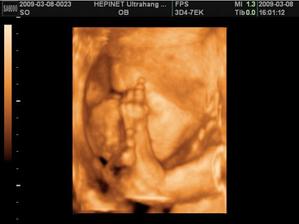

Naša bambuľka Nela

Tak už som tu. Ponáhľala som sa na svet, ale na poslednú chvíľu som si to rozmyslela, tak museli maminke robiť sekciu. Bráško ma dostal ako "darček" za vysvedčko. Neviem, či je z toho na mäkko, ale asi ma ľúbi, keď ma stále bozkáva.....veď si na seba čoskoro zvykneme.